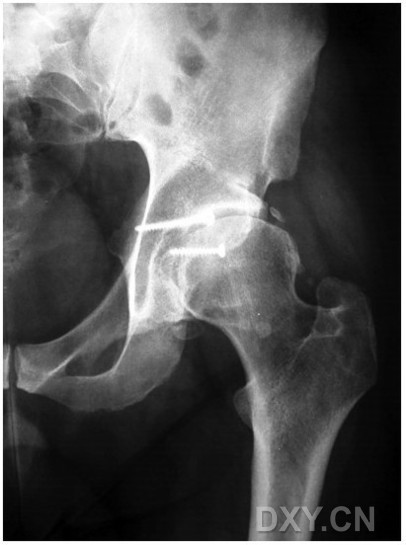

圖 4:與圖1為同一患者,術(shù)后18年,患髖功能較好,活動(dòng)無障礙;影像學(xué)評(píng)估有輕度的骨關(guān)節(jié)炎。